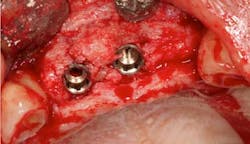

Fig. 11

From a restorative perspective, now that the implants were placed in a restoratively driven manner, the main considerations were to address the patient’s malocclusion and correct her edge-to-edge bite while delivering optimal esthetics. In order to accomplish this goal, a framework was fabricated with a wax-up on the casts. (Fig. 14) By utilizing this method at the framework try-in visit, we were able to give the patient an extremely accurate preview of what her final prosthetic would look like.